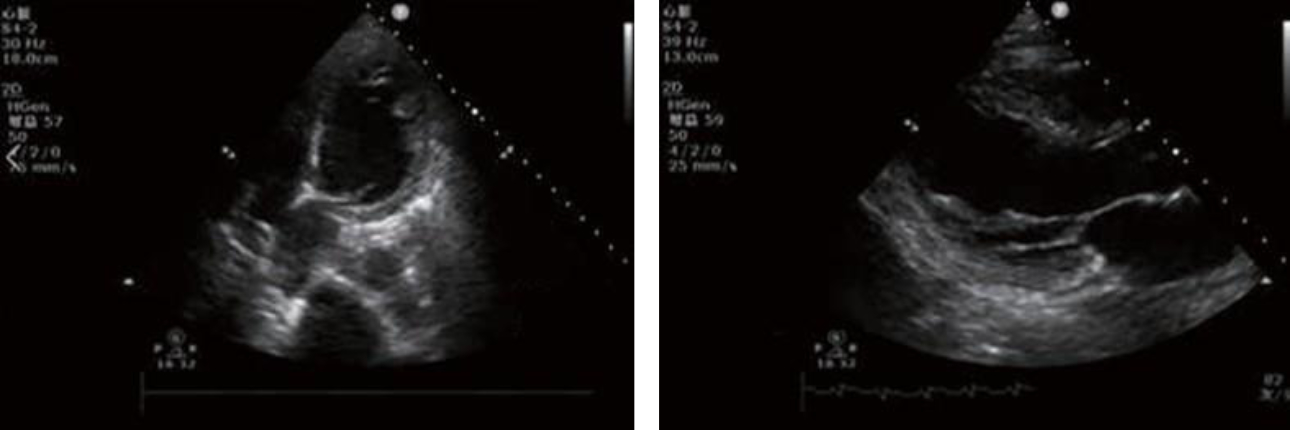

Echocardiography:

Heart function parameters: LVDd: 48 mm

LVEF: 20%M-mode

2-DE: normal dimension of atrium-ventricle, no enlargement of the ascending aorta, an obvious primary wave, a clear dicroitic wave, and a clearly visible aortic valve that opened and closed normally; a slender mitral valve composed of an anterior leaflet with two waves, and a posterior leaflet moving in the opposite direction to the anterior leaflet.

Ventricular wall thickening is absent, and movement of the ventricular septum and the posterior wall of the left ventricle is in opposite directions.

Obvious attenuation of beats of the middle segment and apex of the left ventricle at rest, and fair motility of its base.

DOPPLER: Color Doppler ultrasound showed signals of small amounts of regurgitation through the mitral and tricuspid valves.

Diagnostic comments: Decreased left ventricular systolic function (LVEF: 20%), Takotsubo syndrome (stress cardiomyopathy) to be excluded, and mild mitral and tricuspid regurgitation.

Based on the ultrasonographic findings (obvious attenuation of beats of the middle segment and apex of the left ventricle, i.e., a similar shape of an ŌĆ£octopus potŌĆØ)?and negative coronary angiographic findings, the patient was diagnosed with Takotsubo syndrome. However, repeated abnormal fluctuations in IBP were observed in the patient, therefore, pheochromocytoma was also simultaneously considered.